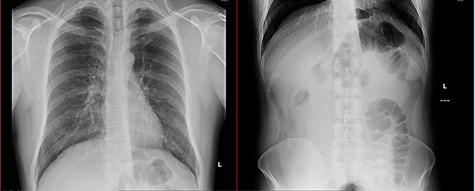

Two days later, for the persistence of symptoms, an abdomen computed tomography (CT) scan and surgical evaluation were required. The patient presented abdominal distension, tenderness without peritoneal signs, nausea and vomiting, but reported similar episodes auto-resolved abdominal in the past. The scan revealed a prominent gastrectasia, dilatation of duodenum and the first jejunal branch and jejunal mural edema was discovered, referable to an ischemic suffering, but there was no evidence of free air. The diagnosis was proximal bowel mechanical obstruction with suspect ischemic loop (Figs 2 and 3), so a surgical operation was proposed and the patients agreed.

The preoperative CT was reviewed, considering intraoperative findings, and an incomplete bowel rotation was highlighted: duodenojejunal loop was abnormally located on the right side of abdomen and cecum was positioned at the left of mesentery, as illustrated in Fig. 2.